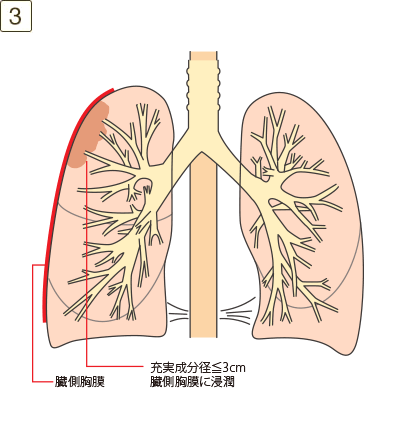

充実成分径>3cmでかつ≦5cm、または充実成分径≦3cmでも以下のいずれかであるもの

- ・臓側胸膜に浸潤